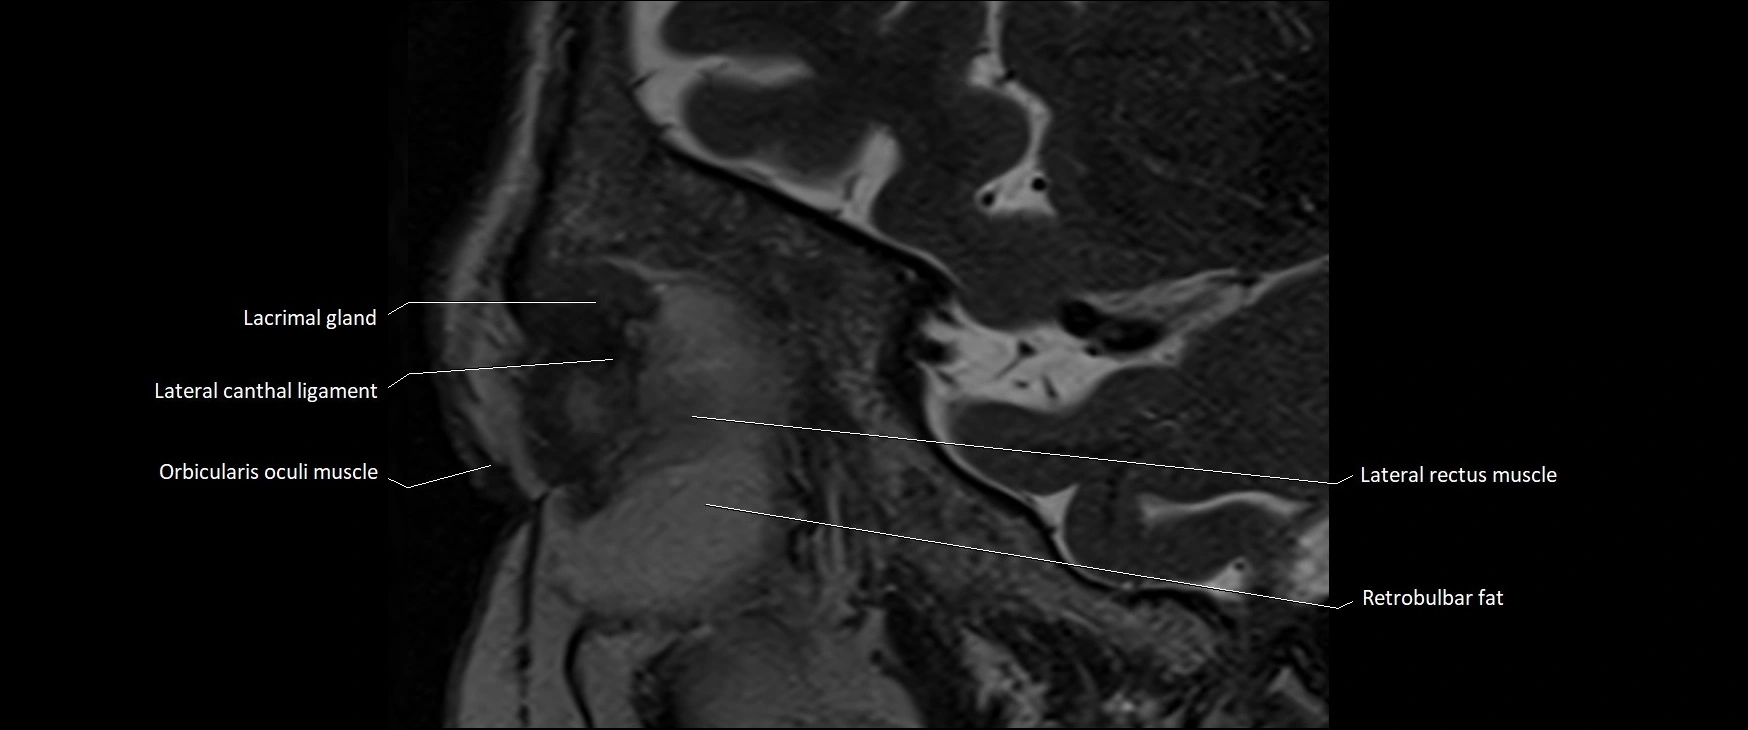

- Lacrimal gland

- Lateral canthal ligament

- Lateral rectus muscle

- Orbicularis oculi muscle

- Retrobulbar fat